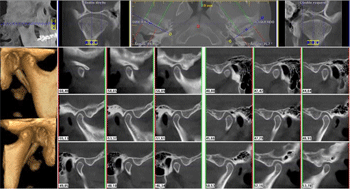

Ortho X - Tomografia de ATM

Tem a finalidade de evidenciar o processo condilar em vista lateral ou frontal, em boca aberta ou fechada. É indicada para verificação de fraturas ou desgaste do côndilo.